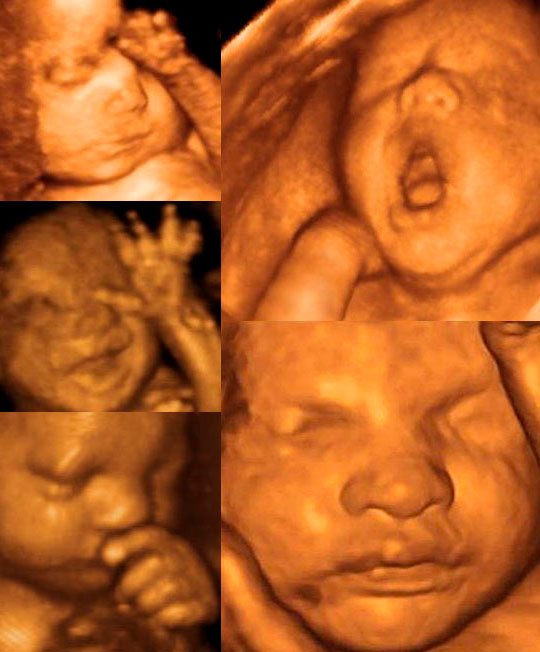

Хотите увидеть, как улыбается ваш малыш ещё до его рождения? 4D УЗИ поможет вам в этом!

При проведении 4D УЗИ при беременности вы увидите объемное изображение, внешность вашего малыша в деталях, его эмоции — радость, огорчение или апатию.

4D УЗИ дает возможность увидеть будущего ребенка еще до его рождения максимально реалистично, сделать фото плода, запечатлеть движения, эмоции (грустит малыш или улыбается, машет ручкой), рассмотреть отдельно все органы и части тела (ручки и ножки: проверить наличие пяти пальчиков на каждой из конечностей, увидеть личико и т.д.), узнать пол малыша. У вас есть возможность увидеть форму рта и носа ребенка, как он зевает или показывает язык, попытаться предположить, на кого он больше похож — на маму или на папу.